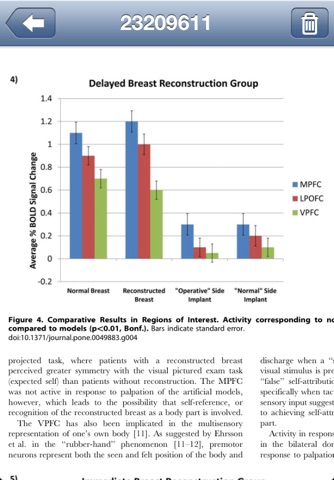

PubMed Library is designed to search and organize all your favorite articles on the go. PubMed comprises more than 19 million citations for biomedical literature from MEDLINE, life science journals, and online books that you can search from almost anywhere. Citations may include links to full-text content from PubMed Central and publisher web sites.

With PubMed Library you can make advanced searchs to PubMed, download available information of articles you are interested in, access and / or download full text of the article, download and attach a PDF file to a downloaded article, share downloaded article information by mail and many more.